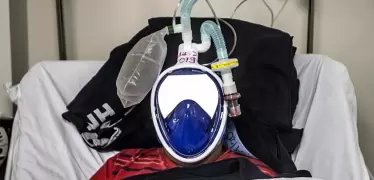

مغاربة يبتكرون جهازا يكشف سلبية كورونا في 20 ثانية